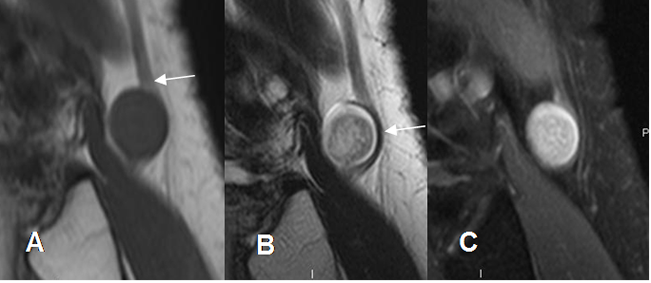

Fig 178 B. Schwanoma.

A: RM coronal en T2 y B: RM coronal en T1 con contraste. Lesión redondeada y de bordes bien definidos, sobre los músculos aductores. Tiene consistencia mixta con áreas quísticas y realce del contraste en las zonas sólidas.

C: RM axial en STIR. Se identifica nivel líquido-líquido, por sangrado.